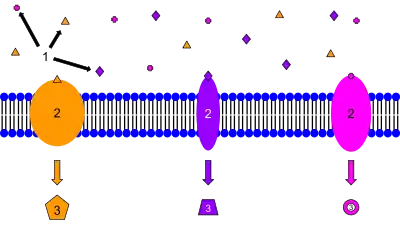

Protein–ligand complexes can be found in almost any cellular process. Binding of a ligand causes a conformational change in the protein and often also in the ligand. This change initiates a sequence of events leading to different cellular functions. The complexes are formed by different molecules like macromolecules as in protein complexes, protein DNA or protein RNA complexes as well as by proteins that bind smaller molecules like peptides, lipids, carbohydrates, small nucleic acids. They may have various functions within the cell: catalysis of chemical reactions (enzyme-substrate), defense of the organism through the immune system (antibodies antigen complexes), signal transduction (receptor-ligand complexes) that consists of a transmembrane receptor that upon binding the ligand activates an intracellular cascade. Lipophilic hormonal receptor complexes can pass the nuclear membrane where transcription may be regulated.[8]

Protein-Ligand complex is essential in many of the cellular processes that occur within organisms. One of these examples is the Glucagon receptor (GCGR). Glucagon receptor (GCGR) is a family of G-protein coupled receptors (GPCRs) in humans that plays an important role in maintaining glucose concentration within the blood during periods of low energy state. Glucagon binding to GPCRcauses a conformational change in the intracellular domain, allowing interaction with the heterotrimeric Gs protein. The alpha Subunit of the Gs protein releases bound GDP and binds GTP. The alpha subunit-GTP complex dissociates from the beta and gamma dimer and interacts with adenylate cyclase. Binding of glucagon molecule activates many of the alpha subunit, which amplifies the hormonal signal. Then, the alpha subunit activates the adenylate cyclase, which converts ATP to cAMP. The alpha subunit deactivates itself within minutes by hydrolyzing GTP to GDP (GTPase activity). The alpha subunit reassociates with beta-gamma dimer to form an inactive complex. A better understanding of the protein-ligand complex mechanisms may allow us for the treatment of some diseases such as type 2 diabetes.[10] Glucagon receptor inhibitors are promising for the treatment of type 2 diabetes.[11] Inhibitors of Glucagon receptors are either glucagon neutralizers or small molecular antagonists, and they all rely on the concept of protein-ligand complex interaction.[11]